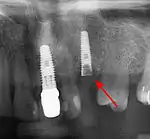

Panorex radiograph showing implants

Xray of four Straumann implants and abutments